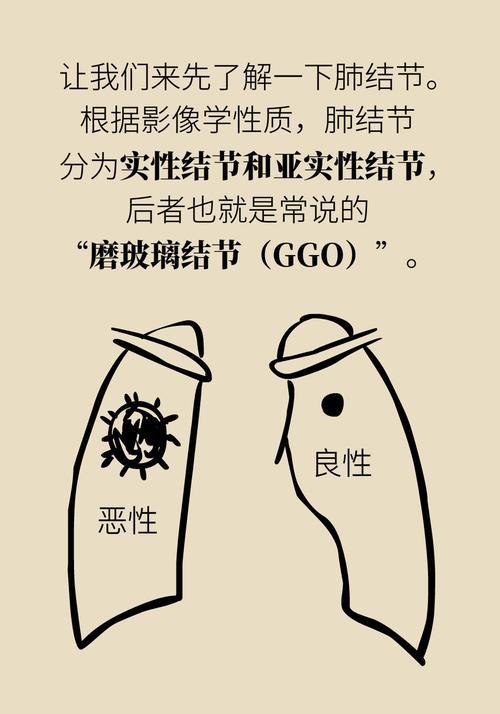

肺结节属于正气不足,痰湿阻塞经络循行、气血不通畅产生结节或淤滞。

中医认为,肺结节的形成多因正气亏虚,痰湿、血瘀积在肺部,气虚、气滞、痰、瘀四者互相影响,导致脏腑功能失调,天长日久积聚而成。中医调理肺结节,一定要因人而异,辨证对待。可以通过使用清肺、润肺、除痰、解郁、软坚、散结的药物、食物,促使肺结节变小,甚至消失。